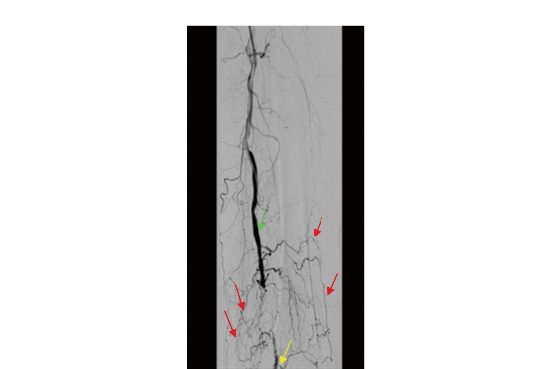

Измерение ЛПССК проводилось одним исследователем. Пациент укладывался в положение лежа на спине, после 10–15 минут покоя при комнатной температуре 21–23°С проводилось измерение ЛПССК. Для регистрации ЛПССК датчик ультразвукового аппарата устанавливался на уровне тыльной артерии стопы (ТАС) и задней большеберцовой артерии (ЗББА) дистальнее медиальной лодыжки (рис. 1).

Рис. 1. Уровень измерения спектральных характеристик кровотока по тыльной артерии стопы и задней большеберцовой артерии (ангиограмма правой стопы).

При развитии препятствия току крови в артериях (окклюзии артерий) запускается адаптационный механизм – артериогенез, который приводит к расширению уже существующих коллатеральных сосудов (рис. 8). Ведущими силами многоступенчатого процесса формирования коллатеральных артерий [14] являются артериальное давление, градиент давления выше и ниже уровня окклюзии и сила напряжения сдвига на стенки моделирующегося сосуда. Исходом артериогенеза является 20–50-кратное увеличение предшествующих артерий [15], которое может частично компенсировать работу магистральных артерий и снижать тяжесть ишемии нижних конечностей.

Рис. 8. Ангиограмма артерий нижней конечности пациента с сахарным диабетом и критической ишемией конечности. Зеленой стрелкой указан нормальный кровоток в поверхностной бедренной артерии, красными стрелками указаны коллатеральные сосуды, желтой – кровоток в дистальном сегменте артерии.